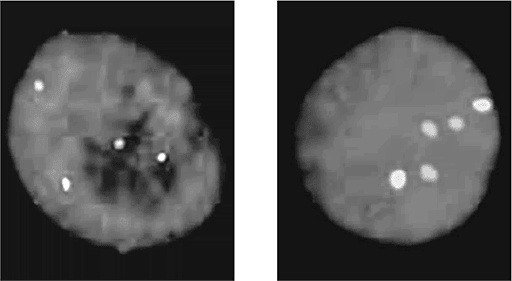

Через пятьдесят лет после появления теста забора крови из пятки у новорожденных Роберт Грин и его коллеги из Гарвардской медицинской школы запустили Baby Seq – рандомизированное клиническое исследование, в рамках которого планируется отсеквенировать геномы более сотни новорожденных и отследить в них 1700 заболеваний, начинающихся в детском возрасте. Для Гарварда это всего лишь небольшое клиническое исследование, но оно даст возможность совершить огромный скачок в оценке пользы от всеобщего скрининга новорожденных. На 1950-е годы пришлось активное развитие цитогенетики – изучения хромосом под микроскопом. В диагностической практике этот подход показал, что при нарушении числа хромосом, когда их больше или меньше нормы, неизбежно возникают тяжелейшие болезни. Проблемы связаны с дисбалансом числа генов, то есть с отклонением от нормы «по два гена от каждого». Подобные расстройства не передаются по наследству, как миодистрофия Дюшенна или муковисцидоз, но все равно являются по сути генетическими; они возникают спонтанно при сбоях в клеточном делении и при образовании дефектных сперматозоидов и яйцеклеток. Наиболее известная из таких болезней – синдром Дауна. Названа болезнь в честь Джона Лэнгдона Дауна, который в 1866 году впервые описал его характерные клинические признаки. «…Это [внешнее сходство] столь выраженное, что, если посадить таких детей бок о бок, сложно поверить, что они из разных семей». Девяносто лет спустя французский врач Жером Лежен обнаружил, что у детей с синдромом Дауна по три экземпляра одной хромосомы (впоследствии выяснилось, что лишняя 21-я хромосома). Среди генетиков-профессионалов такое расстройство именуется «трисомия 21». ![]() Трисомия 21 (синдром Дауна). Кариотип (полный набор хромосом), взятый у мужчины с синдромом Дауна. Обратите внимание на лишнюю 21-ю хромосому Чем старше мать, тем выше риск синдрома Дауна. Когда матери 20, вероятность родить такого ребенка составляет примерно 1:1700, когда 35 – уже 1:400, а в 45 достигает 1:30. Именно поэтому многие старородящие женщины выбирают пренатальную диагностику, позволяющую определить, есть ли у плода тройная 21-я хромосома. Сегодня такой анализ входит в стандарт обследования беременных женщин старше 35 лет. В Великобритании 30 % беременностей с синдромом Дауна обнаруживается при плановом тестировании у 5 % самых старородящих женщин. Этот метод выделяется своей высокой эффективностью по соотношению «число обнаруженных случаев на каждый потраченный фунт стерлингов», но что насчет остальных 70 % случаев синдрома Дауна? Неинвазивные методы являются альтернативными умеренно рискованным технологиям: амниоцентезу и биопсии хориона, – меняют профиль пренатальной диагностики. В конце 1990-х годов различные исследователи, в частности Деннис Ло из Китайского университета в Гонконге, показали, что ДНК плода можно обнаружить в плазме крови матери. Десять лет спустя Ло и группа ученых из Стэнфордского университета под руководством Стивена Квейка независимо показали, что анализ такой ДНК позволяет выявить трисомию 21. Процедура под названием «неинвазивное пренатальное тестирование» (NIPT) относительно проста: исследователь секвенирует 5–10 миллионов коротких произвольно взятых фрагментов ДНК из материнской плазмы, а затем сличает их с соответствующими хромосомами. Если в ДНК плода обнаруживается лишняя 21-я хромосома, то из 21-й хромосомы будет больше фрагментов, чем из других. Аналогично обнаруживаются трисомии и в других хромосомах, в частности в 13-й или 18-й. Такие трисомии вызывают соответственно синдром Эдвардса и синдром Патау, тяжелые генетические расстройства; ребенок с такими болезнями обычно умирает спустя несколько недель или месяцев после рождения. Другие трисомии летальны на пренатальном этапе, так прерывается около 30 % беременностей, и около половины подобных случаев прерывания беременности связаны с теми или иными хромосомными аберрациями. Точность и эффективность метода неинвазивного пренатального тестирования (NIPT) была доказана в ходе клинических исследований, и первый клинический анализ по такому методу диагностики был выставлен в 2011 году. Вскоре появились и другие, и NIPT стал стандартной диагностической пренатальной процедурой, которую обычно проходят на первых 10 неделях беременности. Увы, этот метод не абсолютно точен. В 2014 году в Атланте был зафиксирован первый «ложноотрицательный» результат NIPT: ребенок родился с синдромом Дауна, хотя диагностика показала, что плод здоров. Пока скрининг ДНК плода, взятой из плазмы материнской крови, позволяет выявить лишь ограниченный набор генетических расстройств. ![]() Флуоресцентное окрашивание, позволяющее определить число хромосом. Ядро клетки (синее) анализируется на присутствие 10-й хромосомы (голубая) и 21-й хромосомы (розовая). Слева показан нормальный кариотип, в котором по два экземпляра обеих этих хромосом; справа – кариотип, соответствующий синдрому Дауна (три 21-х хромосомы) ![]() Симон – итальянский студент, страдающий синдромом Дауна. Снимок предоставлен Positive Exposure – некоммерческой организацией, цель которой – поддержка «особенных» людей, стремящихся вести нормальную жизнь Однако, по мнению Джея Шендью (Jay Shendure), врача-исследователя из Вашингтонского университета, вскоре появится возможность считывать по такой ДНК всю геномную последовательность плода. Джей Шендью с коллегами предложили метод неинвазивного взятия образцов материнской ДНК и сравнения этого материала с геномными последовательностями родителей. Так с высокой точностью удается определить геномную последовательность плода. Проблемы остаются, но, как заявил Джей Шендью в беседе с журналистом New York Times, «…это уже не научная фантастика». По мере того как генетические анализы становятся все более сложными, открывается ящик Пандоры с этическими дилеммами. Подоплека их далеко не ограничивается исходными проблемами, для решения которых разрабатывался анализ, а последствия касаются не только тех людей, которые такой анализ сдают. Ни в какой другой отрасли медицины эта проблема не проявляется так очевидно, как при генетических анализах в семьях с заболеваниями, передающимися по наследству, например миодистрофией Дюшенна, болезнью Хантингтона или муковисцидозом. Недавно мужчина в возрасте за двадцать попросил проверить его на болезнь Хантингтона. Его дед по отцу умер от этой болезни, а отец, которому было уже за сорок, решил не сдавать анализ, предпочтя, подобно Нэнси Векслер, жить с пятидесятипроцентной неопределенностью, а не знать наверняка. Поскольку болезнь Хантингтона обычно поражает пожилых, существовала вероятность, что и у отца есть такая мутация, просто симптомы еще не проявились. Молодой человек понимал, что у него вероятность [19] такой мутации (и, соответственно, вероятность заболеть в будущем) составляет 1 к 4. Но он хотел знать, что его ждет. Проблема состоит вот в чем: если мутацию у сына обнаружат, то получить ее он мог только от отца, и, следовательно, отца болезнь неизбежно настигнет. Стремление сына доискаться генетической правды прямо противоречит нежеланию отца ее знать. Отец с сыном рассорились, и в конце концов, после долгих уговоров матери, сын отказался от анализа. Мать убедила сына в том, что его желание знать правду меркнет по сравнению с правом отца защититься от информации, которая может стать для того смертным приговором. Этот драматический пример показывает, как сильно генетический анализ отличается от любого иного. Любая информация, которую я могу узнать о моих генах, отразится на моих биологических родственниках независимо от того, хотят ли они ее знать или предпочитают скрыть. |